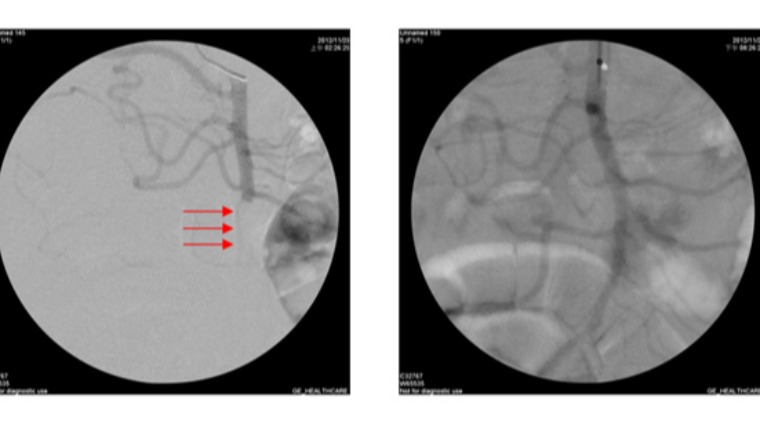

▲左圖:血管攝影顯示上腸繫膜動脈阻塞。右圖:經治療後血管又恢復暢通。

由於陳老太太曾有心房纖維顫動的情況於門診追蹤,經詳細檢查才發現,上腸繫膜動脈發生阻塞,情況十分危急。因此當夜立即安排溶栓導管手術,將導管放到阻塞血管處,並給予血栓溶解劑。